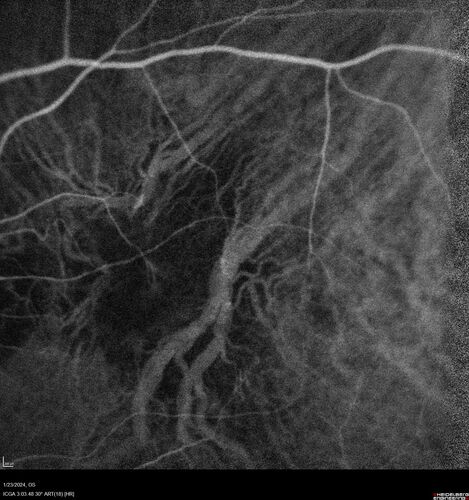

wet AMD with classic extrafoveal macular neovascularization in the good eye

89 year old man with longstanding vision loss in the left eye presented with one month of mild vision loss in the right eye.  Vision was 20/32.  This eye responded to vabysmo therapy.